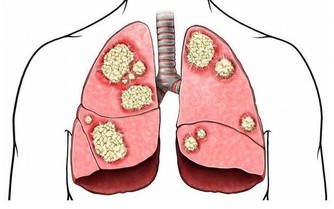

人們都說肝病猛於虎,如果患上肝病又沒有及時治療的話,很容易就會發展成肝硬化,更嚴重就會轉變為肝癌,增加了治療的難度,甚至危及到生命健康。肝病患者只要積極的配合醫生治療,就能夠延緩向肝癌發展的進程。其實比起治療肝病,做好肝病的預防更能從源頭上切斷患病機率,而且飲食調理至關重要。

慢性肝炎是指由不同病因引起的,病程至少持續超過6個月以上的肝臟壞死和炎症。不同類型的慢性肝炎的臨床表現大多相同,如乏力、噁心、食慾減退、腹脹等等,病程呈波動性或持續進行性,如不進行適當的治療,部分患者可進展為肝硬化。

肝硬化是臨床常見的慢性進行性肝病,由一種或多種病因長期或反復作用形成的瀰漫性肝損害。在我國大多數為肝炎後肝硬化,少部分為酒精性肝硬化和血吸蟲性肝硬化。